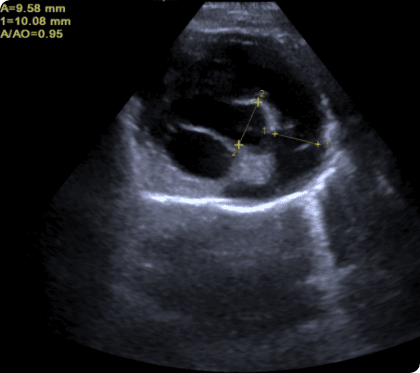

CT 혈관조영, 심장초음파 등 고사양 영상장비를 활용하여

혈관 구조와 병변을 정밀 분석, 최적의 수술 계획을 수립

간문맥단락은 간으로 가야 할 혈액이 전신으로 우회하는

비정상 혈관.

해독되지 못한 물질이 퍼져 발작 등 신경 증상을 유발하며,

조기 진단과 수술 교정이 필수적임.